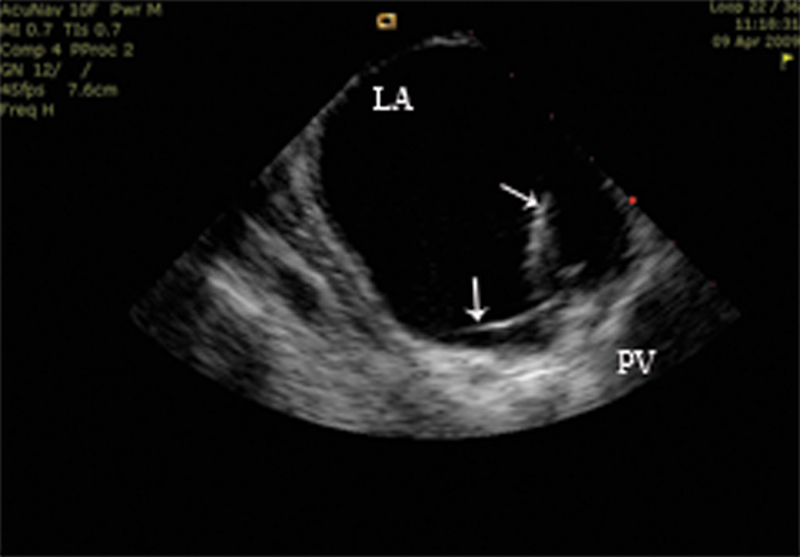

فحوصات تشخيصية لبعض امراض القلب والشرايين التاجية